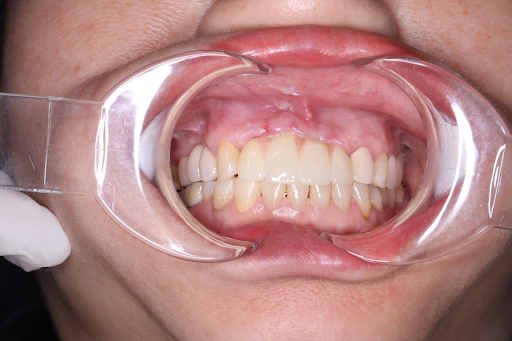

Khách hàng sau khi cấy ghép Implant tại nha khoa Dr.SmileCare

Nếu bạn đang tìm kiếm địa chỉ cấy ghép Implant uy tín tại TP.HCM, Nha khoa Dr.SmileCare tại Quận Gò Vấp là một lựa chọn đáng tin cậy. Với đội ngũ bác sĩ chuyên môn cao và trang thiết bị hiện đại, Dr.SmileCare cam kết mang đến dịch vụ cấy ghép Implant an toàn và hiệu quả. Đội ngũ bác sĩ tại Nha khoa Dr.SmileCare có kinh nghiệm lâu năm trong lĩnh vực cấy ghép Implant, đảm bảo mang lại sự hài lòng cho khách hàng.